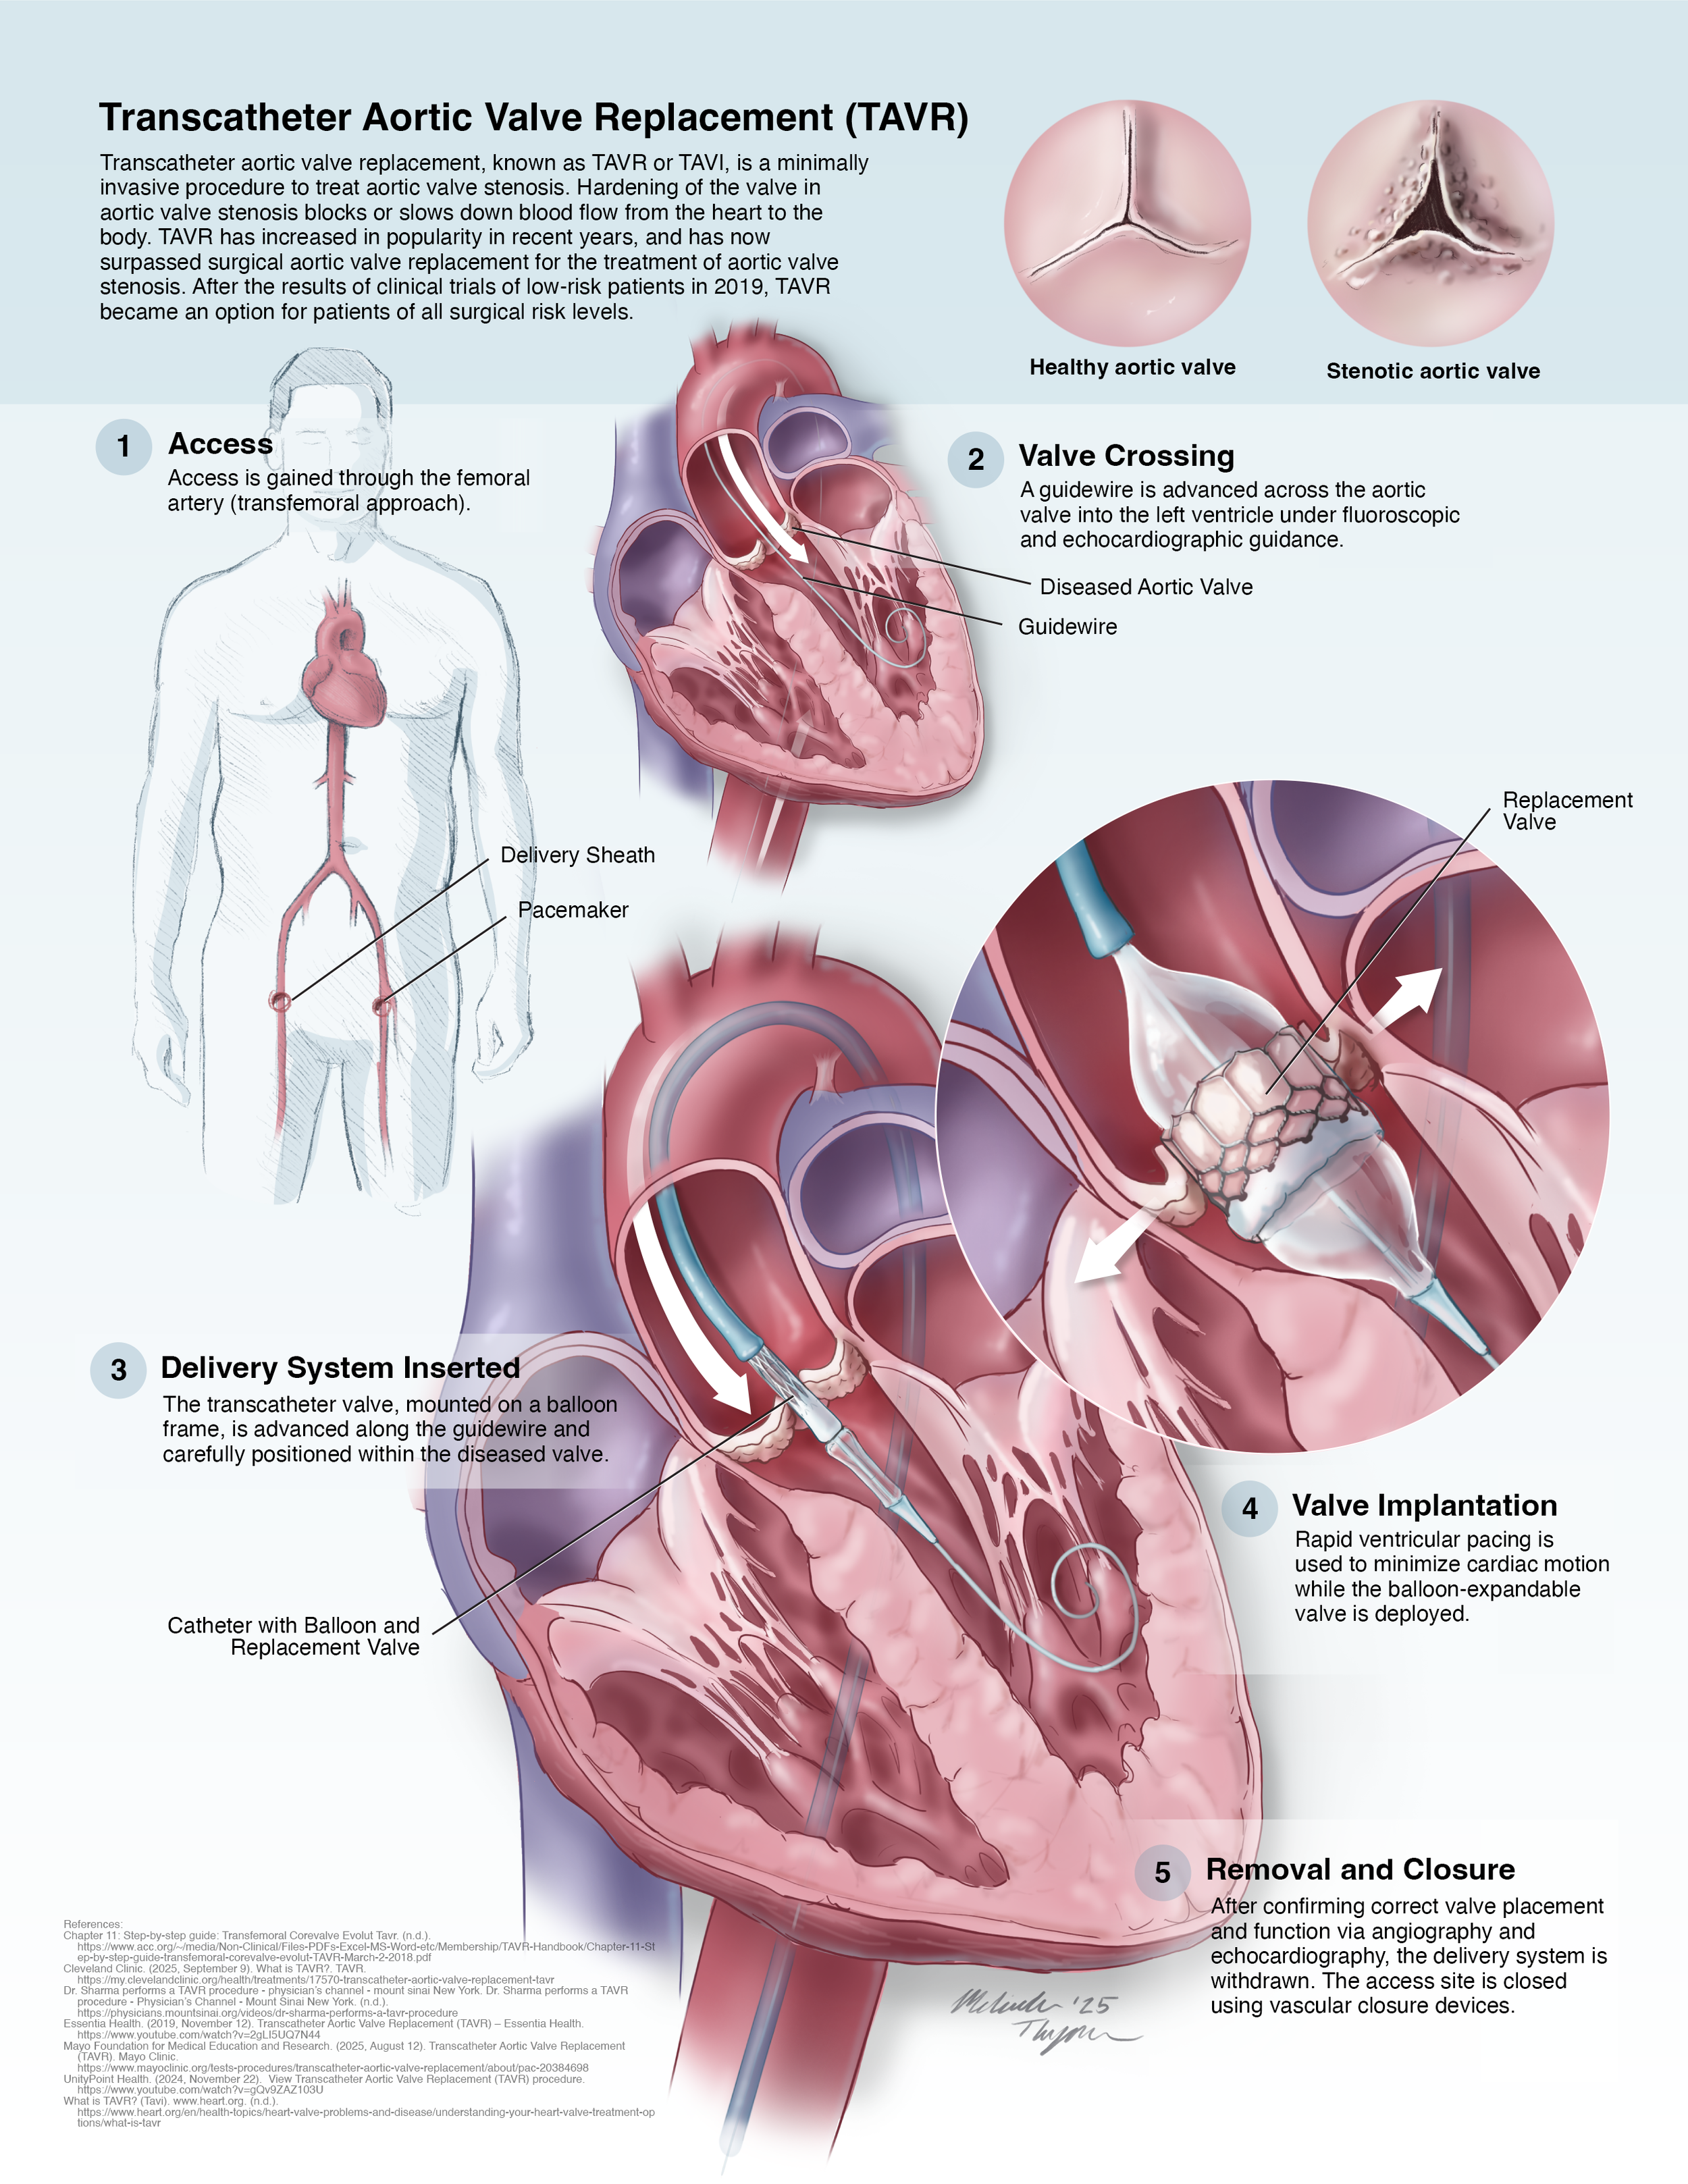

Academic Surgical Illustration: Transcatheter Aortic Valve Replacement - Illustrated Procedure